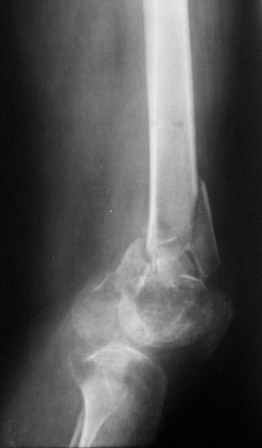

Re: Несросшийсз перелом дистального эпиметафиза бедра

Отправитель: Коваленко А.Н. 16 Январь 2006, 01:50

Вторую проекцию (качества получше) отправил. Наши возможности ограничены Chm, я тоже хотел бы антеградно, но гвоздей с такими отверстиями нет, а канюлированный рассверливать не хочется. Отсутствие ЭОПа принуждает к использованию канюлированных гвоздей.